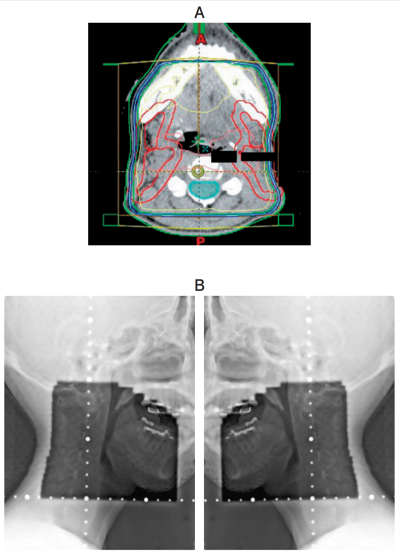

口腔癌における術後照射の治療計画時の線量分布、照射野の写真及び治療装置の写真を別に示す。治療法はどれか。1つ選べ。

a. 電子線照射

b. モールド照射

c. 低線量率組織内照射

d. 高線量率組織内照射

e. エックス線外部照射